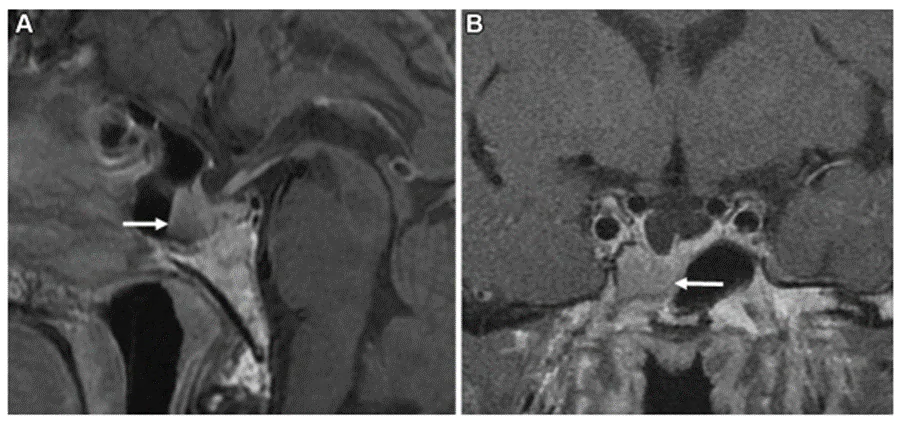

中枢性尿崩症は、下垂体腫瘍の症状の一つです。また、下垂体腫瘍を摘出した際の周術期合併症の一つで、下垂体後葉からのバゾプレッシン分泌障害により発症します。バゾプレッシンはMRIのT1強調画像で下垂体後葉の高信号により存在が示されます。下垂体柄の高信号の形態によって尿崩症からの回復時期が予測できることを報告しました (Hayashi Y et al. Pituitary 2016)。また、ラトケ嚢胞においても尿崩症で発症する症例を解析し、発症の特徴と予後について報告しています(Oishi M et al. Clin Neurol Neurosurg 2018)。現在は下垂体後葉から分泌されるバゾプレシンのほかにオキシトシンについても着目し、MRI画像との関連について研究しています。

ラトケ嚢胞の内容成分と病理所見

(Oishi M et al. Clin Neurol Neurosurg 2018)